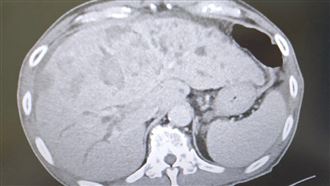

▲萬芳醫院耳鼻喉科主治醫師丁義芳解說喉癌。(圖/記者蔡杰翰攝影)